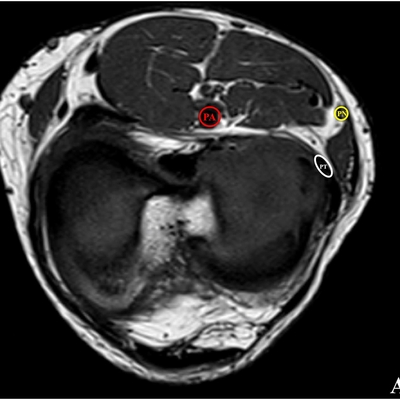

Click on an image below to view more info.